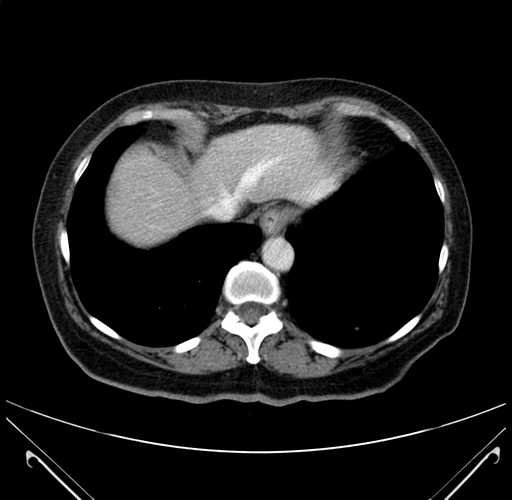

Pre-Chemo: Axial Venous

Axial Venous